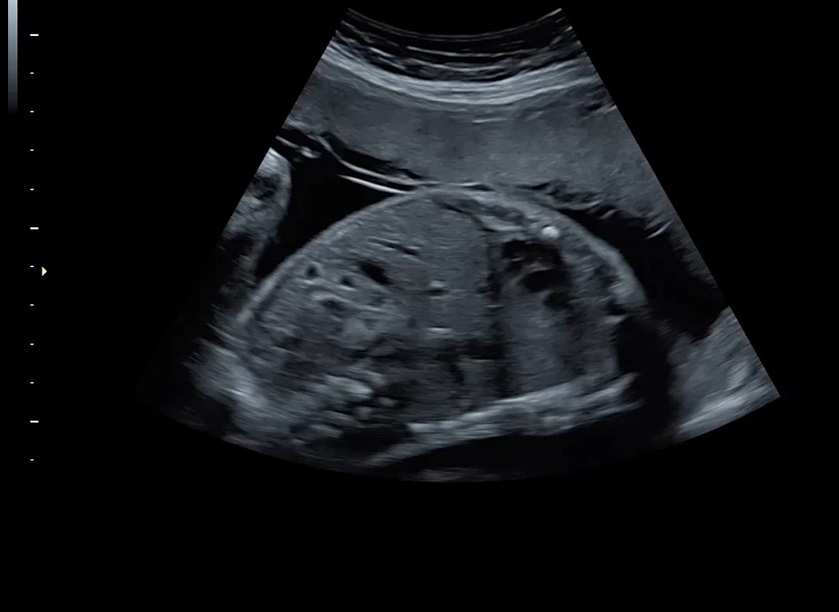

Ультразвуковая платформа Voluson S8 представляет собой оборудование экспертного класса с передовыми возможностями и высоким уровнем автоматизации процессов. Она позволяет проводить сканирование в режимах 2D, 3D и 4D с высоким качеством изображений.

Аппарат Voluson S8 базируется на надежной платформе VCA, которая имеет множество положительных отзывов. Она обладает высококонтрастной технологией объемной реконструкции, обеспечивая качественное воспроизведение изображений. Информация выводится на широкоформатный цветной монитор размером 23 дюйма для убедительной демонстрации плода будущим родителям и облегчения работы врача.

• Высокое качество изображений: Voluson S8 обеспечивает высококачественные изображения, позволяющие детально оценить состояние плода и обнаружить возможные патологии.

• Технология автоматической фетометрии в 2D режиме (SonoBiometry): Эта технология позволяет автоматически измерять бипариетальный размер, окружность головы, окружность живота, длину бедра и плеча плода, обеспечивая точные и надежные измерения.